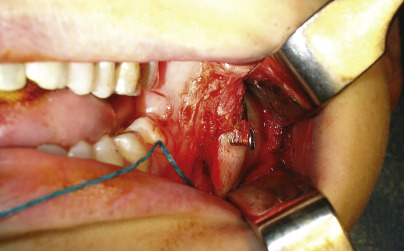

Sagittal split osteotomy of the deficient mandible with advancement in the sagittal plane may result in ramus asymmetry and border irregularities ( Figs. 15.1 and 15.2 ). Ramus asymmetry immediately after surgery occurs when the surgeon fails to create similar osteotomies and maintain similar osteotomy gaps (with rigid fixation) on both sides. The surgeon loses control over the relation of the proximal and distal fragments because the condyle must be positioned in its fossa and the body must be positioned to correct the occlusion. The positioning of these two areas dictates ramus and angle position. In the orthognathic literature, the concern for the improper positioning of the proximal segments and condyle relates to its potential for condylar resorption and postoperative relapse. In the pre-rigid fixation era this was almost always due to counterclockwise rotation of the ramus of the mandible because wire osteosynthesis did not provide enough stability. Rigid fixation has virtually eliminated these problems related to inadequate fixation.

However, contour abnormalities may still occur due to incorrect positioning with resultant counterclockwise rotation or after very large movements. Clinical experience has revealed that this is due to not only the positional restraints of condylar positioning and osteotomy variability as described above, but also ramus shape changes resulting from bone atrophy ( Fig. 15.3 ). Depending on the circumstance, this atrophy may result from devascularization and/or remodeling from altered mechanotransduction forces in accordance with Wolff’s Law.

Gaps at the osteotomy sites after sagittal osteotomy of the mandible or horizontal osteotomies of the chin with advancement can result in border irregularities. Correction of contour irregularities after skeletal rearrangement have focused on border defects at the sliding genioplasty osteotomy site, prompting some surgeons to fill the defect with hydroxyapatite. Surgical technique and the native mandible anatomy determine the presence and severity of these irregularities.